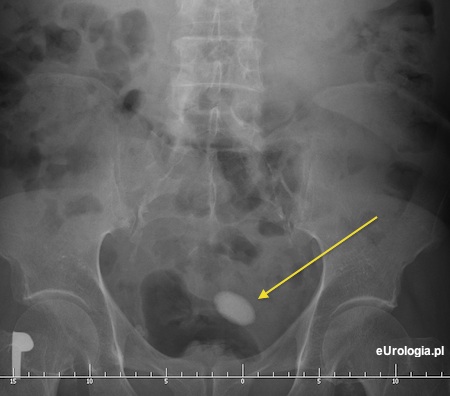

Podstawowym badaniem wykonywanym w celu rozpzoznania kamicy pecherza moczowego jest badanie USG jamy brzusznej. Dodatkowo możliwe jest wykonanie zdjęcia rentgenowskiego nerek i pęcherza. Czasami istnieje konieczność wykonania cystoskopii kiedy badania obrazowe nie dają jasnej odpowiedzi. Kamień wpęcherzu moczowym jest dobrze widoczny w badaniach obrazowych. Poniżej przykłady kamicy pęcherza moczowego w badaniach obrazowych.

Fot. Cień złogu na zdjęciu przeglądowym jamy brzusznej